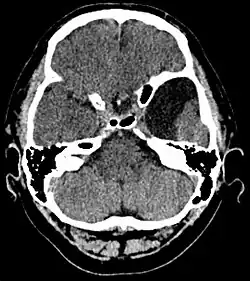

| An MRI of a 25-year-old woman with left frontotemporal arachnoid cyst. | |

Diagnosis is principally by MRI. Frequently, arachnoid cysts are incidental findings on MRI scans performed for other clinical reasons. In practice, diagnosis of symptomatic arachnoid cysts requires symptoms to be present, and many with the disorder never develop symptoms.